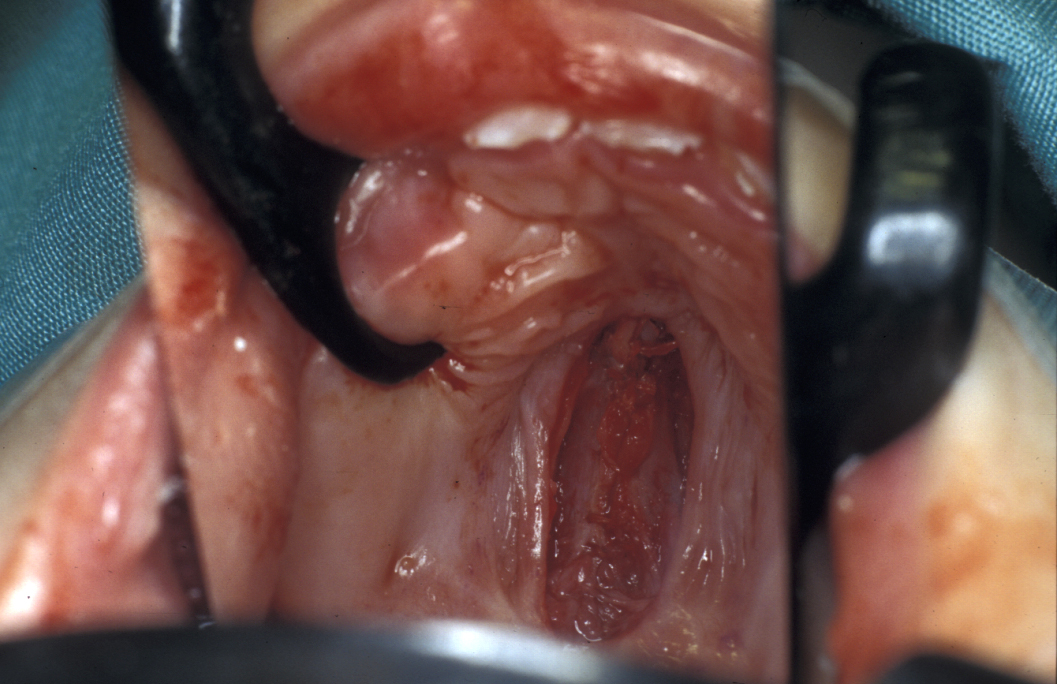

Palatal closure by common consensus is now carried out using techniques which leave minimum stripped palatal mucoperiosteum and exposed bone in an attempt to decrease scarring and the unwanted effects on growth (Figure 4 and Figure 5).

Figure 4: Second-stage closure of the cleft hard palate by using a double-layer technique; the first layer closes the nasal floor.

Figure 5: The second layer closes the oral mucosa and reinforces the first-layer repair.